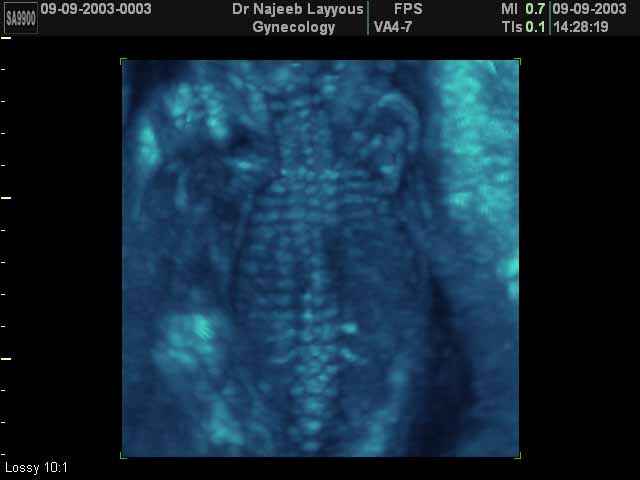

- 3D Photos échographie du squelette du fœtus